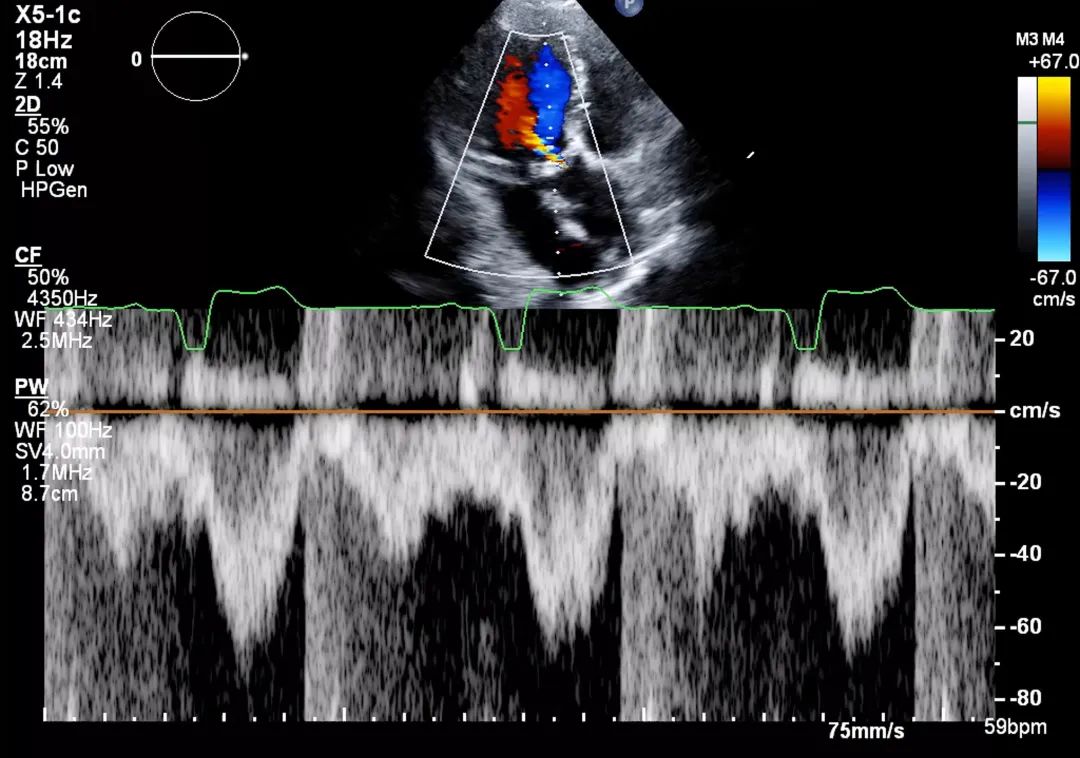

7、心尖五腔心切面: 在主动脉瓣处的彩色多普勒显示主动脉瓣狭窄引起的彩色镶嵌血流(mosaic color flow)模式,且可显示主动脉瓣反流(aortic regurgitation,AR)。应确认湍流起始位置,确保湍流源自瓣膜层面,而非瓣下(如主动脉瓣下隔膜或肥厚型心肌病所致左室流出道梗阻)或瓣上位置(图8,视频5)。

图8. 心尖五腔心切面评价主动脉瓣狭窄(有和彩色多普勒对比)

心尖五腔心切面结合主动脉瓣处彩色多普勒,用于评估流出道梗阻所致狭窄性彩色镶嵌血流模式以及主动脉瓣反流。缩写同图2。

8、心尖五腔心切面:将连续多普勒(continuous-wave Doppler,CW)取样线对准主动脉瓣血流方向,测量主动脉瓣峰值流速和跨瓣压差,并评估是否存在主动脉瓣反流。测量主动脉瓣峰值流速波形(图9)。

图9. 心尖五腔心切面连续多普勒评估

心尖五腔心切面:将连续多普勒取样线对准主动脉瓣血流方向,测量主动脉瓣峰值流速(A)和跨瓣压差,并评估主动脉瓣反流(B)。

9、心尖五腔心切面: 将脉冲多普勒(pulse wave Doppler,PW)取样容积(sample volume)置于左室流出道,注意避免放置在血流汇聚区(flow convergence area)(图10)。操作时,可先将脉冲多普勒取样容积置于主动脉瓣瓣口水平,然后缓慢向心尖方向回撤至左室流出道内,直至获得无混叠且获得清晰居中的频谱多普勒波形。注意取样容积放置过于靠近主动脉瓣瓣叶,可导致高估流速;反之取样容积过于靠近心室侧,则可能低估流速。测量脉冲流速时,应应选择测量频谱波形中最明亮的白色边缘(即众数流速),代表绝大多数血细胞的流速。

图10. 心尖五腔心切面脉冲多普勒评估

心尖五腔心切面:将脉冲多普勒取样容积置于左室流出道,避免放置在血流汇聚区。